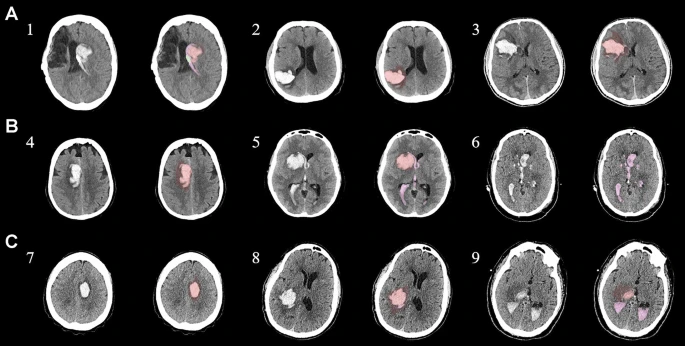

具有臨床特征的探索性成像體積模型分析

ABC/2模型1和模型2分割方法通過ICH和IVH體積的線性回歸顯示出良好的相關(guān)性(圖3a、b)。與模型2分割體積方法(例如,每個(gè)CT15-20分鐘)相比,模型1ABC/2派生的半定量方法和改進(jìn)的Graeb IVH方法完成時(shí)間較短(例如,2-5分鐘)。有趣的是,NIHSS評(píng)分與IVH體積M2方法的比較顯示出線性相關(guān)性(R 2 ?= 0.7217),并且當(dāng)IVH小于20mL或大于20mL時(shí),NIHSS評(píng)分似乎出現(xiàn)聚類(圖3c)。PHE分析顯示MSC注射劑量和PHE體積之間存在輕微的負(fù)相關(guān)關(guān)系。

a,通過模型1ABC/2派生方法與vol模型 2(分割)進(jìn)行的神經(jīng)影像ICH vol的線性回歸。b、IVH通過模型1和定量分割模型2方法對(duì)Graeb進(jìn)行了修改。c,出血量和NIHSS評(píng)分與IVH量通過分割進(jìn)行比較。